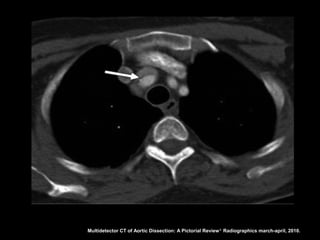

Angiotomografia

Diagnóstico: identificação do flap intimal, que se

apresenta como uma fina membrana separando a

luz falsa da verdadeira;

Sensibilidade e especifidade acima de 95% na

detecção do flap intimal;

Multidetector CT of Aortic Dissection: A Pictorial Review 1. Radiographics march-april, 2010.